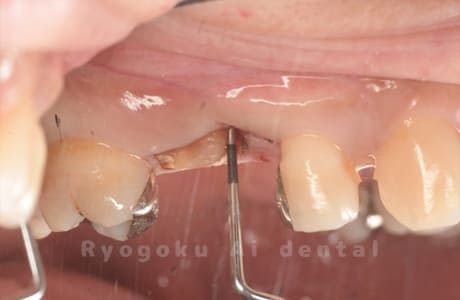

Case27

-

重度カリエス

歯牙移植咬合面術前 -

移植する親知らず

歯牙移植術直後咬合面

歯牙移植術後咬合面

歯牙移植術前側面

歯牙移植術中側面

歯牙移植術後側面

- 原因

- 重度カリエス

- 治療内容

- 自家歯牙移植、部分矯正

- 治療費用

- 220,000円(移植費用)

110,000円(部分矯正費用)

虫歯が大きく、保存不可能となった歯を上の親知らずと交換する自家歯牙移植を行いました。移植歯が小ぶりであったため、部分矯正を行い問題なく噛み合い、経過良好です。